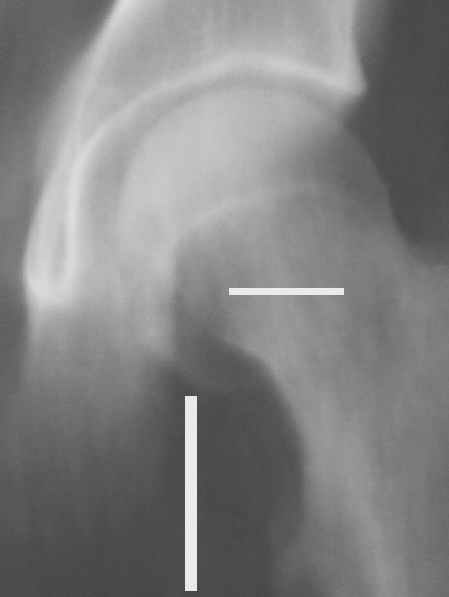

Уважаемые коллеги! Заканчивая обследование больного с переломо-вывихом бедра сделал ему обычные R-томограммы. Кажется удалось "поймать" и отломок и донорское место. Мои выводы - в скиаграмме. Считаю, что это передне-нижний фрагмент головки, образовавшийся вследствии отрывного перелома. На томограммах отломок обозначаю длинной стрелкой, а место откуда он оторвался - более короткой. Учитывая тот факт, что его размеры по КТ 25 х 15 мм считаю, что его фиксация на место необходима для профилактики артроза, что при 16-ти летнем возрасте пациента важно в плане максимального отодвигания эндопротезирования. Планирую оперировать его 24.05.05 г. Результаты представлю.

Прямой 19.05

Несколько соображений к "картинкам". На прямом снимке и КТ-томограммах все типичные линии вертлужной впадины: крыша, передняя стенка, задняя стенка - сохранены. На КТ-сканах 6 и 7 появляется фрагментация головки. С учетом R-томограмм отломок расположен спереди-снизу, а не сзади-сверху от сустава, как написано в описании КТ.